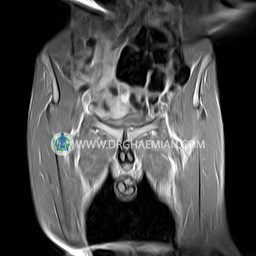

HIP JOINT MRI

( without contrast )

Technique : coronal STIR , coronal T2 , Axial T1 , axial T2 .

REPORT:

The femoral heads and acetabula are normal shape , signal intensity and the femoral heads are well covered by the acetabular margins .

The joint spaces are of normal width without fluid collection .

The articular surfaces are smooth and congruent and show normal cortical thickness .

Each femoral shaft has normal margins and contains a normal bone marrow signal .

The imaged muscles and the lesser pelvis show no abnormalities .

– Heterogeneous signal change (high T2/STIR , low T1) in proximal metaepiphysis of left femur without articular surface irregularity suggestive for bone bruise (stress fracture?), osteomyelitis & arthritis and marrow infiltration (less probable)

– Left hip joint effusion suggestive for synovitis

are seen.

COMMENT: Clinical correlation and MRI with contrast are recommended.